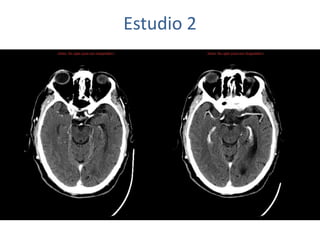

Estudio 2

• Estudio sin y con contraste, con reconstrucciones sagitales y coronales

del estudio con contraste.

Se observa una lesión ocupante de espacio en lóbulo frontal derecho que

presenta un tamaño de 18 x 32 x 22 mm (cc x ap x tr), bilobulada, no del

todo bien delimitada, con realce en anillo irregular, con hipocaptación

central, probablemente por necrosis, y asociada a un extenso edema

vasogénico con efecto masa tanto sobre los surcos de la convexidad

como sobre la cisterna insular, el sistema ventricular y la línea media,

esta última con un desplazamiento de 5 mm a la altura del septo

interventricular.

No se aprecian otras lesiones focales intra o extraaxiales de significación

patológica.

Habría que considerar como primera posibilidad que se tratase de una

lesión metastásica, por bien un tumor primario, aunque no se puede

descartar otras opciones, sin imprescindible correlación con la clínica y

con sus antecedentes.